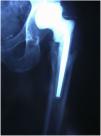

Se decide intervenirlo quirúrgicamente con el fin de evacuar la colección purulenta y limpiar los tejidos infectados. Para esto se aborda la cadera por la vía anterolateral previamente utilizada para la implantación de la prótesis total. Tras el drenaje, la limpieza y la toma de cultivos, se procede a la extracción de la prótesis (ninguno de los componentes estaba movilizado) y a la colocación de un espaciador de cemento con antibiótico (fig. 3).